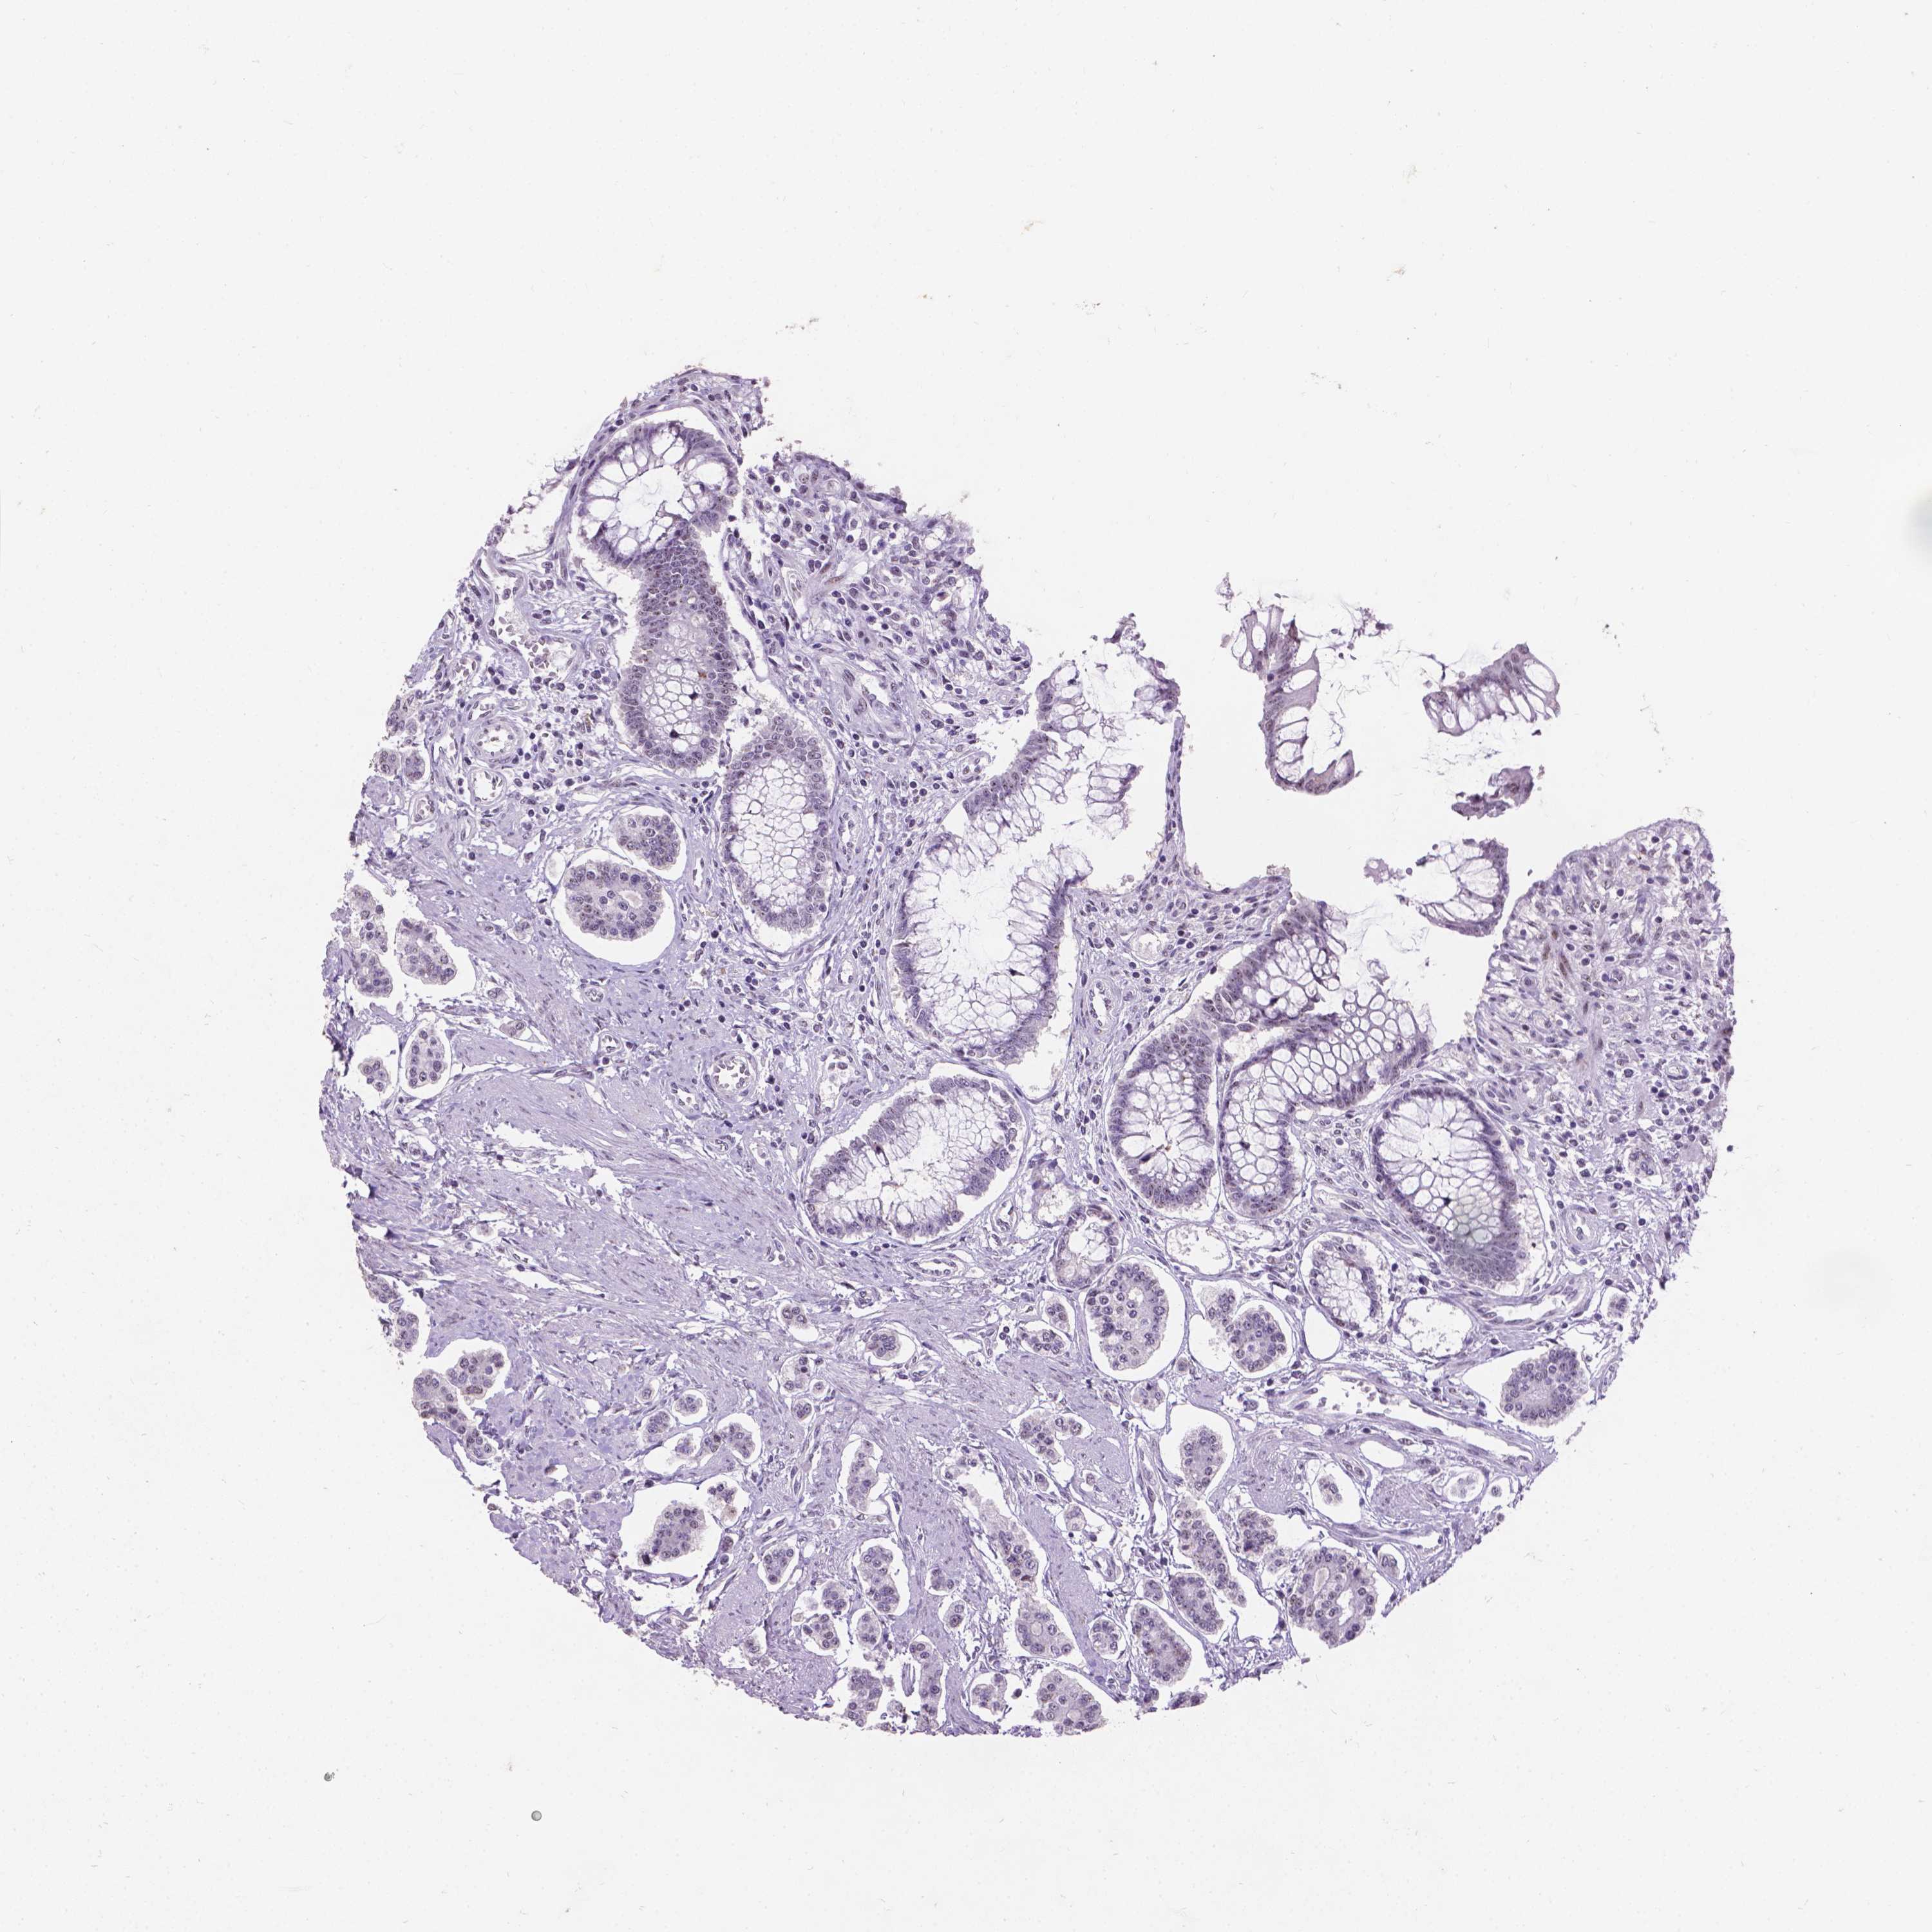

CARCINOID - Protein expressioni

A mouse-over function shows sample information and annotation data. Click on an image to view it in a full screen mode. Samples can be filtered based on level of antibody staining by selecting one or several of the following categories: high, medium, low and not detected. The assay and annotation is described here.

Each image is clickable and will lead to virtual microscopy that enables deeper exploration of all samples and also displays staining intensity scores, fraction scores and subcellular localization as well as patient and tissue information for each sample.

Antibody CAB069400

Staining

High

Intensity

Strong

Quantity

>75%

Location

Nuclear

Carcinoid, malignant, NOS